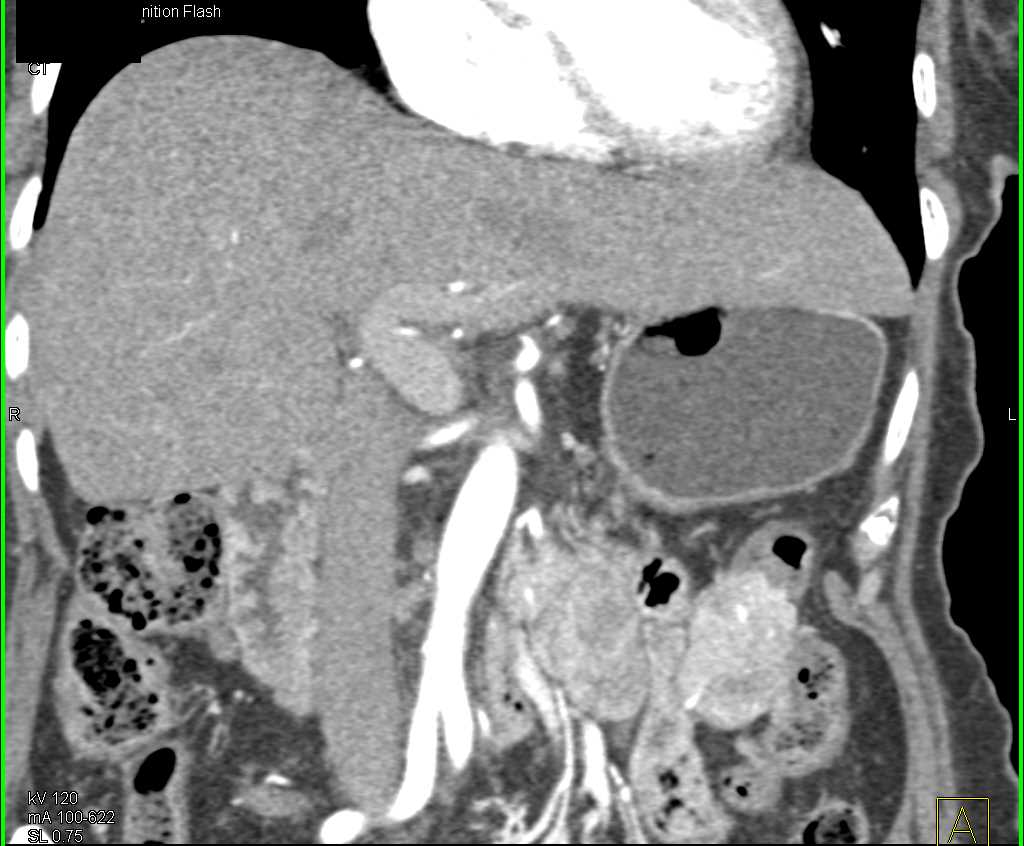

Neuroendocrine Tumor with Superior Mesenteric Vein (SMV) Occlusion